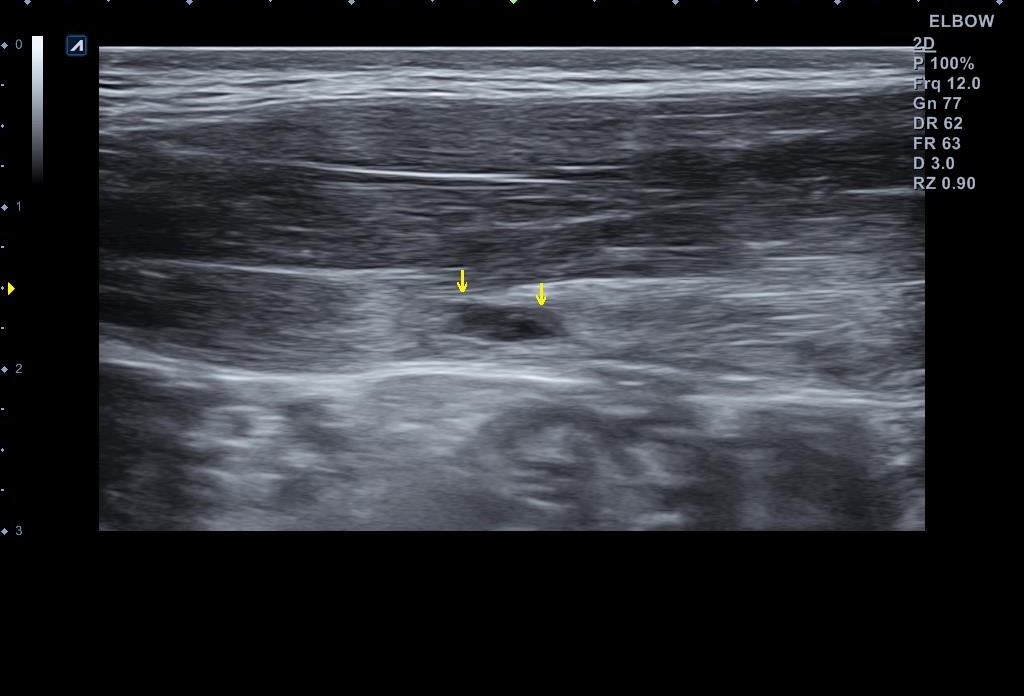

x-ray 검사와 초음파 검사를 진행했습니다. x-ray 검사는 특별한 소견이 없었구요, 초음파 검사는...

나 : 복직근 파열이 맞네요.